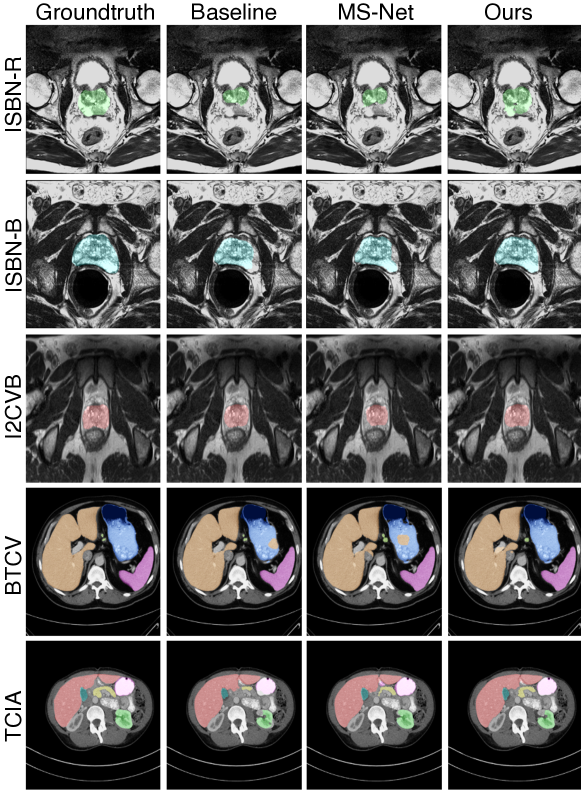

Multi-domain segmentation results: We evaluate our method using the same multi-domain setting as in Liu et al. [19]. To demonstrate the effectiveness of CateNorm, we compare the performance with the baseline and state-of-the-art multi-domain learning methods (i.e., DSBN, MS-Net) on three prostate segmentation datasets and two multi-organ segmentation datasets. As shown in Table 2, under strong data augmentation (e.g., rotation, flipping), DSBN and MS-Net do not yield improvements anymore, while our method still secures a reasonable improvement compared to the baseline. For instance, block 1-4 outperforms the baseline by 0.81%percent0.810.81\% and 1.05%percent1.051.05\% in average Dice on the BTCV and TCIA dataset, respectively. This indicates that, unlike previous methods which customize the normalization layers for different domains [3, 19], our CateNorm can better extract domain-invariant information in the face of a more complex and variable data distribution. Meanwhile, it is also worth mentioning that our approach is complementary to previously domain-specific normalization methods.

Unlike the single-domain setting, block 1-4 outperforms block 1 for both prostate segmentation and multi-organ segmentation. We conjecture that this is due to that given a more complex data distribution, more CNRBs can bring additional benefits by imposing semantic guidance on the encoder more densely. More importantly, our CateNorm is flexible to many popular segmentation architectures such as DeepLabV3+ (see Appendix Table 6). Moreover, CateNorm shows great robustness in partially annotated scenarios—detailed studies are provided in Appendix Figure 3. Qualitative results are in Appendix Figure 4.

Figure 4: Qualitative results comparison. We compare our baseline and the other SOTA method under the multi-domain setting on prostate segmentation and abdominal multi-organ segmentation. Results in the first three rows clearly show that our method outperforms others as their results are cracked and incomplete with these unapparent prostate boundaries. And the results in the last two rows show our methods could better suppress inconsistent class information inside a close segmented area (e.g., reducing false positives inside the stomach) and predict hard organs like the pancreas more accurately by incorporating general and categorical statistics.